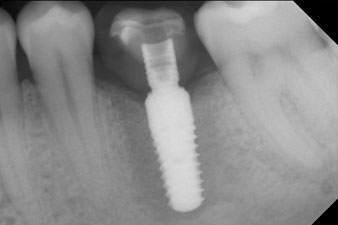

Das Drehmoment beim maschinellen Einbringen war 43 Ncm. Zusätzlich wurde, nach Einschrauben eines speziellen, auf das Implantatsystem abgestimmten Mess-Pfostens (SmartPeg), der ISQ-Wert mit der Sonde des W&H Osstell ISQ Modul bestimmt.

Dieses Modul ist für das Implantmed von W&H optional erhältlich und wird an den Implantologiemotor gedockt (vgl. Abb. 11). Der dimensionslose ISQ-Wert war direkt bei der Insertion 64 in oro-vestibulärer und 68 in mesio-distaler Richtung (Maximalwert = 100). Dies hätte eine offene Einheilung oder sogar Sofortversorgung erlaubt.

Wegen des unzureichenden Knochens krestal am Implantat wurde der Bereich mit den bei der Präparation des Implantatlagers gesammelten Knochenspänen augmentiert und speicheldicht vernäht.